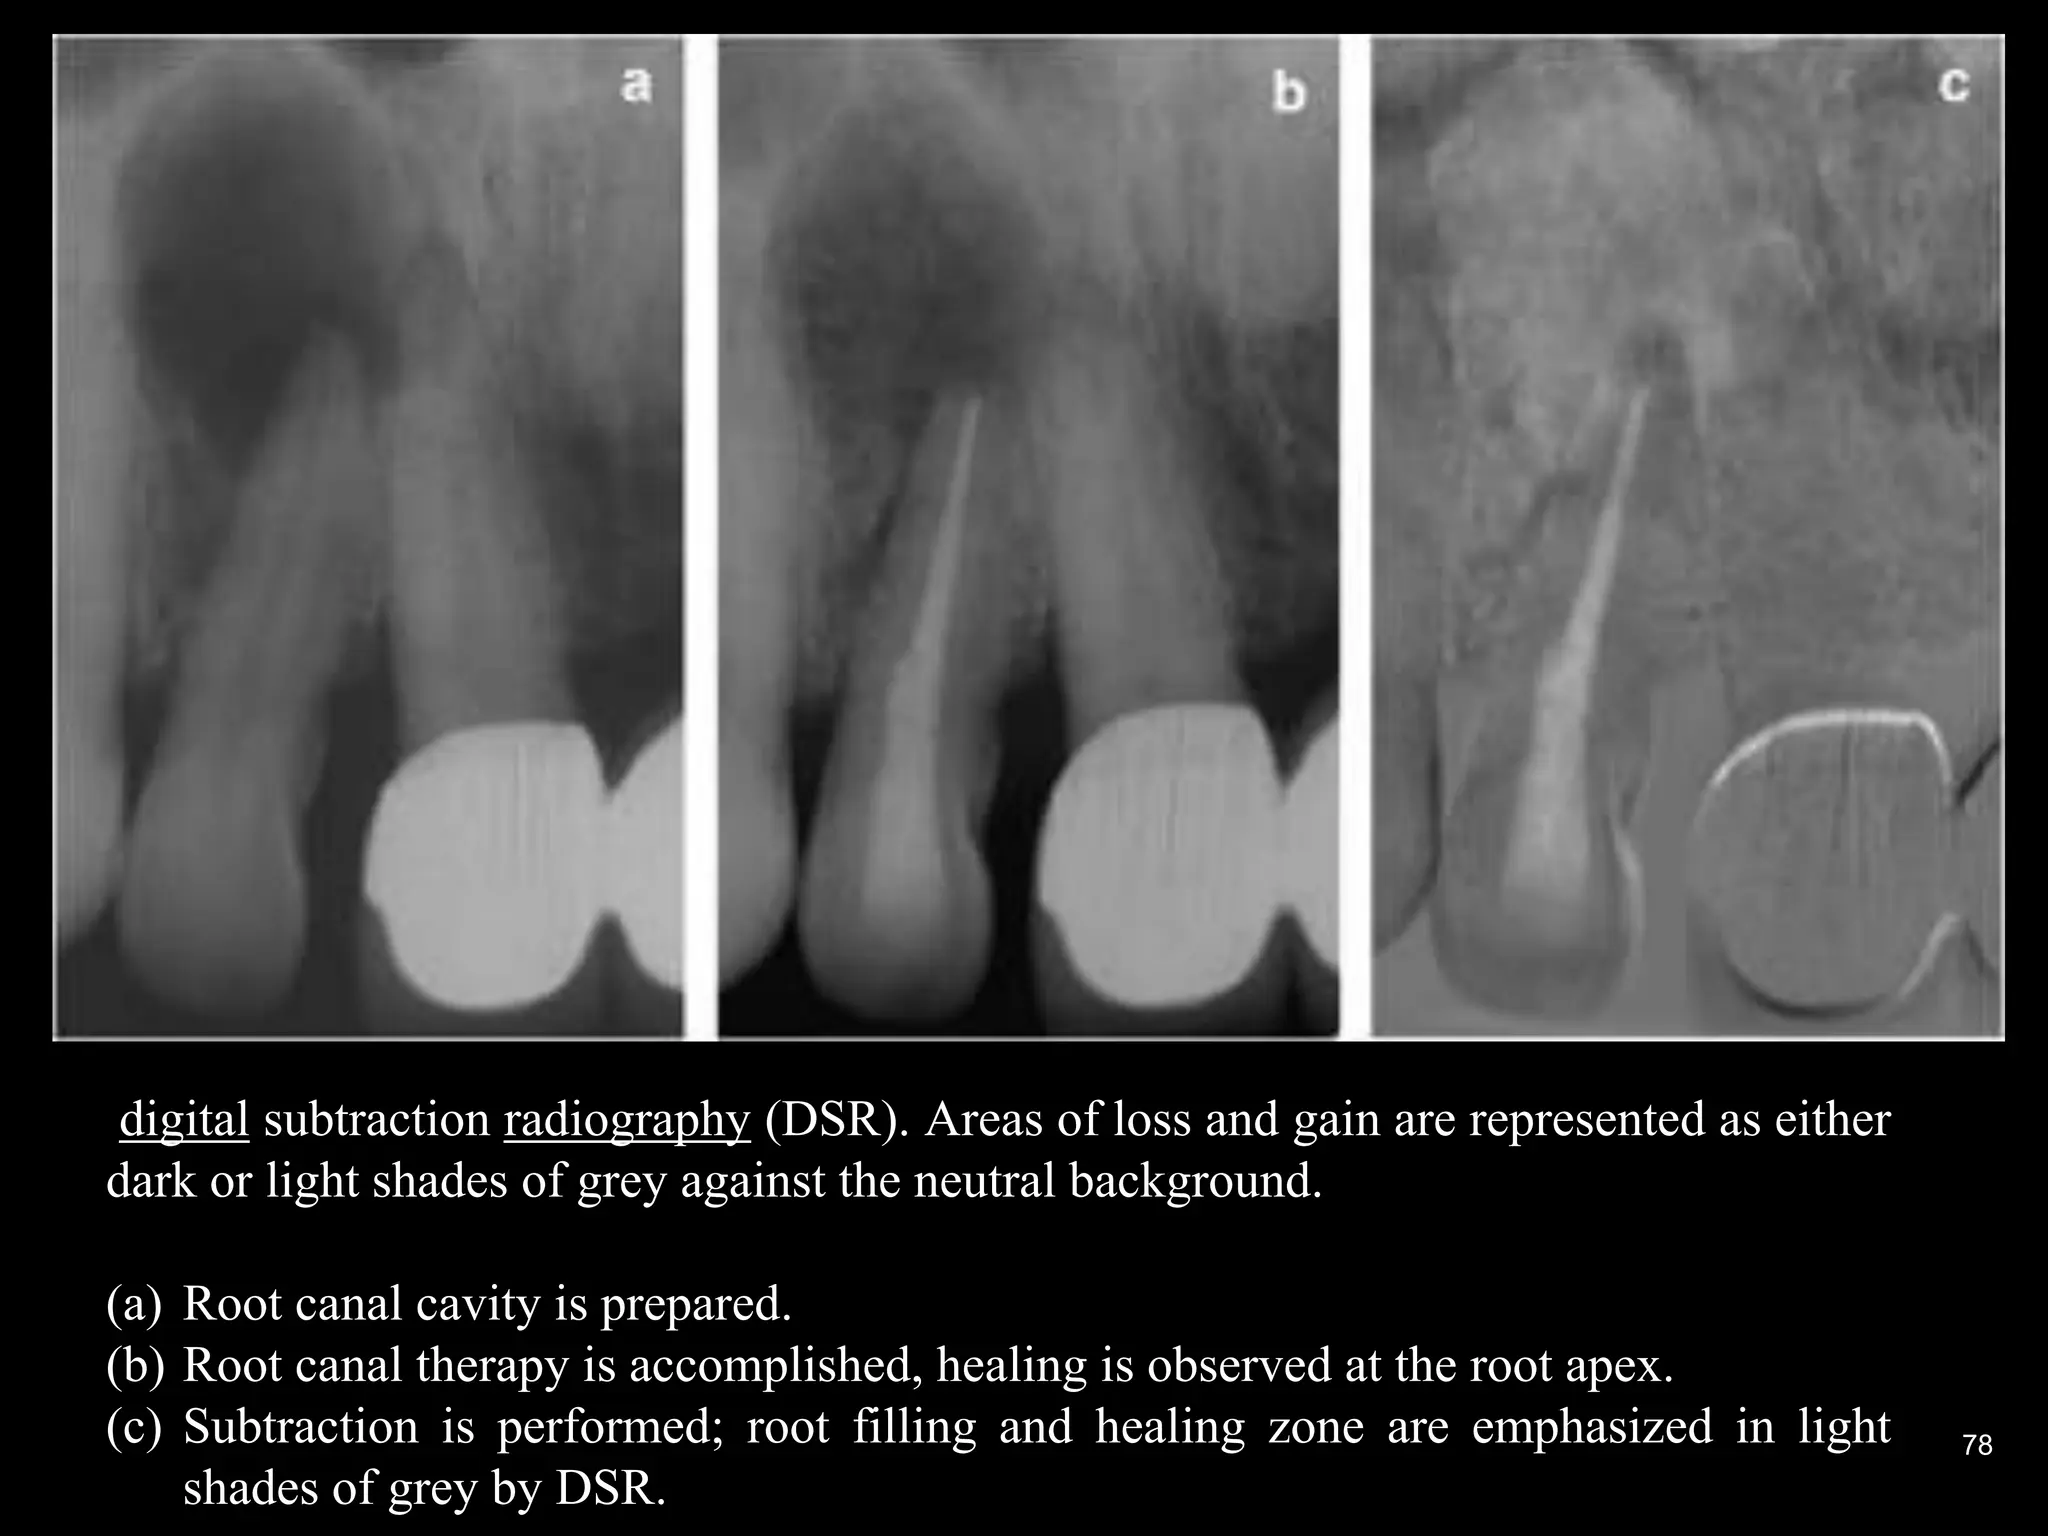

Digital subtraction radiography

77

78

digital subtraction radiography (DSR). Areas of loss and gain are represented as either

dark or light shades of grey against the neutral background.

(a) Root canal cavity is prepared.

(b) Root canal therapy is accomplished, healing is observed at the root apex.

(c) Subtraction is performed; root filling and healing zone are emphasized in light

shades of grey by DSR.

Digital subtraction radiography Subtraction in digital radiology is another image enhancement method with purpose to produce two radiographs of the same area in the mouth at the different time intervals.  The first image can be subtracted from the second one to identify changes that may have occurred during a certain time period. Minimal changes in loss or gain of hard tissue can be detected using this technique, otherwise undetectable by visual examination and traditional radiography. 77

• 78.

78 digital subtraction radiography(DSR). Areas of loss and gain are represented as either dark or light shades of grey against the neutral background. (a) Root canal cavity is prepared. (b) Root canal therapy is accomplished, healing is observed at the root apex. (c) Subtraction is performed; root filling and healing zone are emphasized in light shades of grey by DSR.